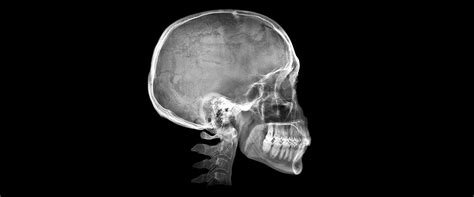

Figura 6 Trazado cefalométrico pretratamiento.

Cefalométricamente, según Ricketts (fig. 6), encontramos un patrón mesofacial, con una maloclusión esquelética de Clase II de origen mandibular, con incisivos inferiores retroinclinados.